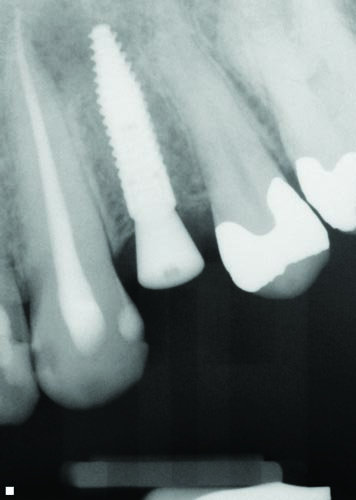

Tools

Fig. 32

Figs. 30–32: Two weeks later, the fourth appointment was reserved for restoration try-in and final impressions on the endosteal implants. It was during the fifth appointment, scheduled for two weeks later, that the implant-supported IPS E.max crown restorations were delivered, as well as the other definitive maxillary restorations, and any necessary adjustments made. These postoperative radiographs confirmed healing at the #3, #12 and #15 sites, which were all ultimately restored with Straumann implants, custom titanium abutments and IPS E.max crowns.